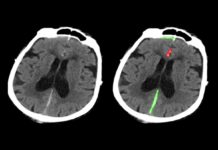

L’intelligenza artificiale può individuare più velocemente le emorragie cerebrali

L’intelligenza artificiale può individuare emorragie cerebrali: aiuta i medici e fa risparmiare tempo prezioso nelle situazioni di emergenza.